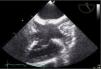

Figure 2.

Transthoracic echocardiogram, apical 4-chamber view, showing thickening of the lead.